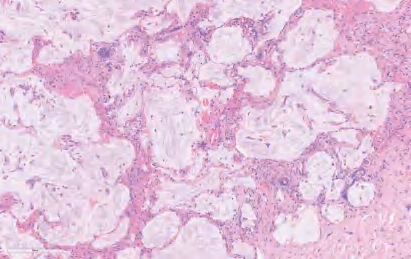

【镜下形态】几乎所有AIS均为非黏液性,通常表现为Ⅱ型肺细胞和(或)Club细胞沿原有肺泡壁连续单层增生,有时可见细胞重叠或轻度分层或微小细胞簇生成,但不存在浸润性生长模式(如腺泡、乳头、微乳头、实性和肺泡腔内存在肿瘤细胞)(图2-2),也不存在间质、脉管、胸膜的浸润及气道播散(STAS)现象。事实上,AIS常存在组织形态改变的多样性,某些区域肿瘤细胞处于缓慢生长或静止甚至退缩状态,肿瘤细胞由于自身凋亡,细胞数量减少,肺泡张力减小,难以维持肺泡结构,伴随肺间隔纤维组织增生,导致部分AIS的腺体内陷,但并非真正的浸润。有些AIS的局部区域肿瘤细胞明显增殖活跃,表现为肿瘤细胞核增大、深染,并突向肺泡腔,但不见核仁,常可见核内包涵体。有时由于切面或制片,可以形成少量的假乳头,这些假乳头成分不是真正的具有二级和三级分支的乳头状结构,因此不能视为浸润性成分。

图2-2 AIS